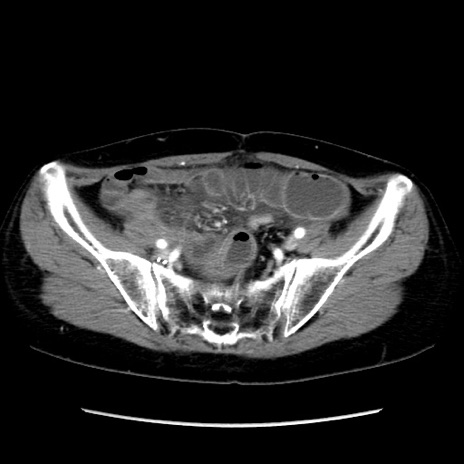

冠状断像